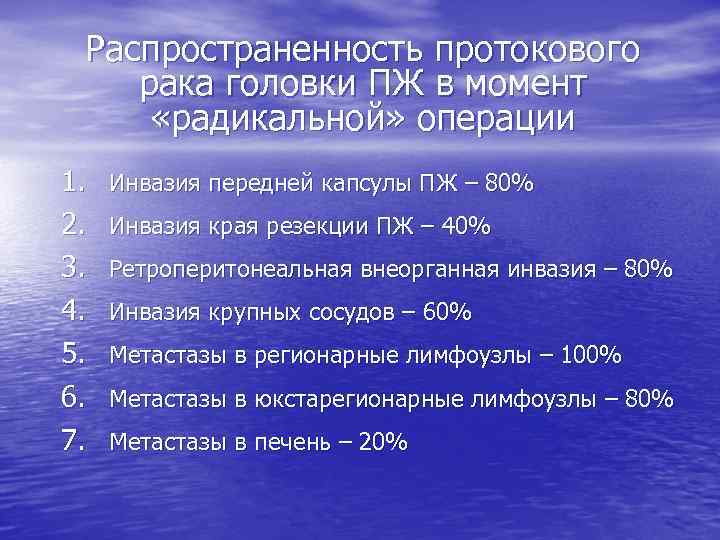

Распространенность протокового рака головки ПЖ в момент «радикальной» операции 1. 2. 3. 4. 5. 6. 7. Инвазия передней капсулы ПЖ – 80% Инвазия края резекции ПЖ – 40% Ретроперитонеальная внеорганная инвазия – 80% Инвазия крупных сосудов – 60% Метастазы в регионарные лимфоузлы – 100% Метастазы в юкстарегионарные лимфоузлы – 80% Метастазы в печень – 20%